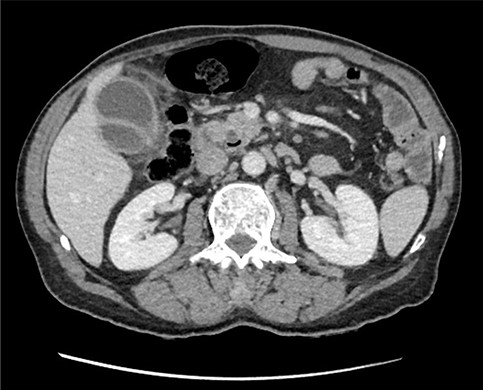

Subsequent review of preoperative imaging solved the mystery. Duplicated gallbladder with double cystic ducts was clearly evident on CT and magnetic resonance imaging (MRI) which were hidden in plain sight (Figs 4–7). CT cholangiogram (Fig. 3) was performed Day 1 post-operatively showing the double cystic duct with no evidence of bile leak. Rest of patient’s admission was uneventful and he was cleared for discharge on Day 5 post-operatively. Patient remains well and was back to his daily activities during his follow-up review.

Axial section of preoperative CT abdomen from initial presentation showing thickened gallbladder with pericholecystic fluid; duplicated gallbladder evident, initially thought to be Phrygian cap sign.